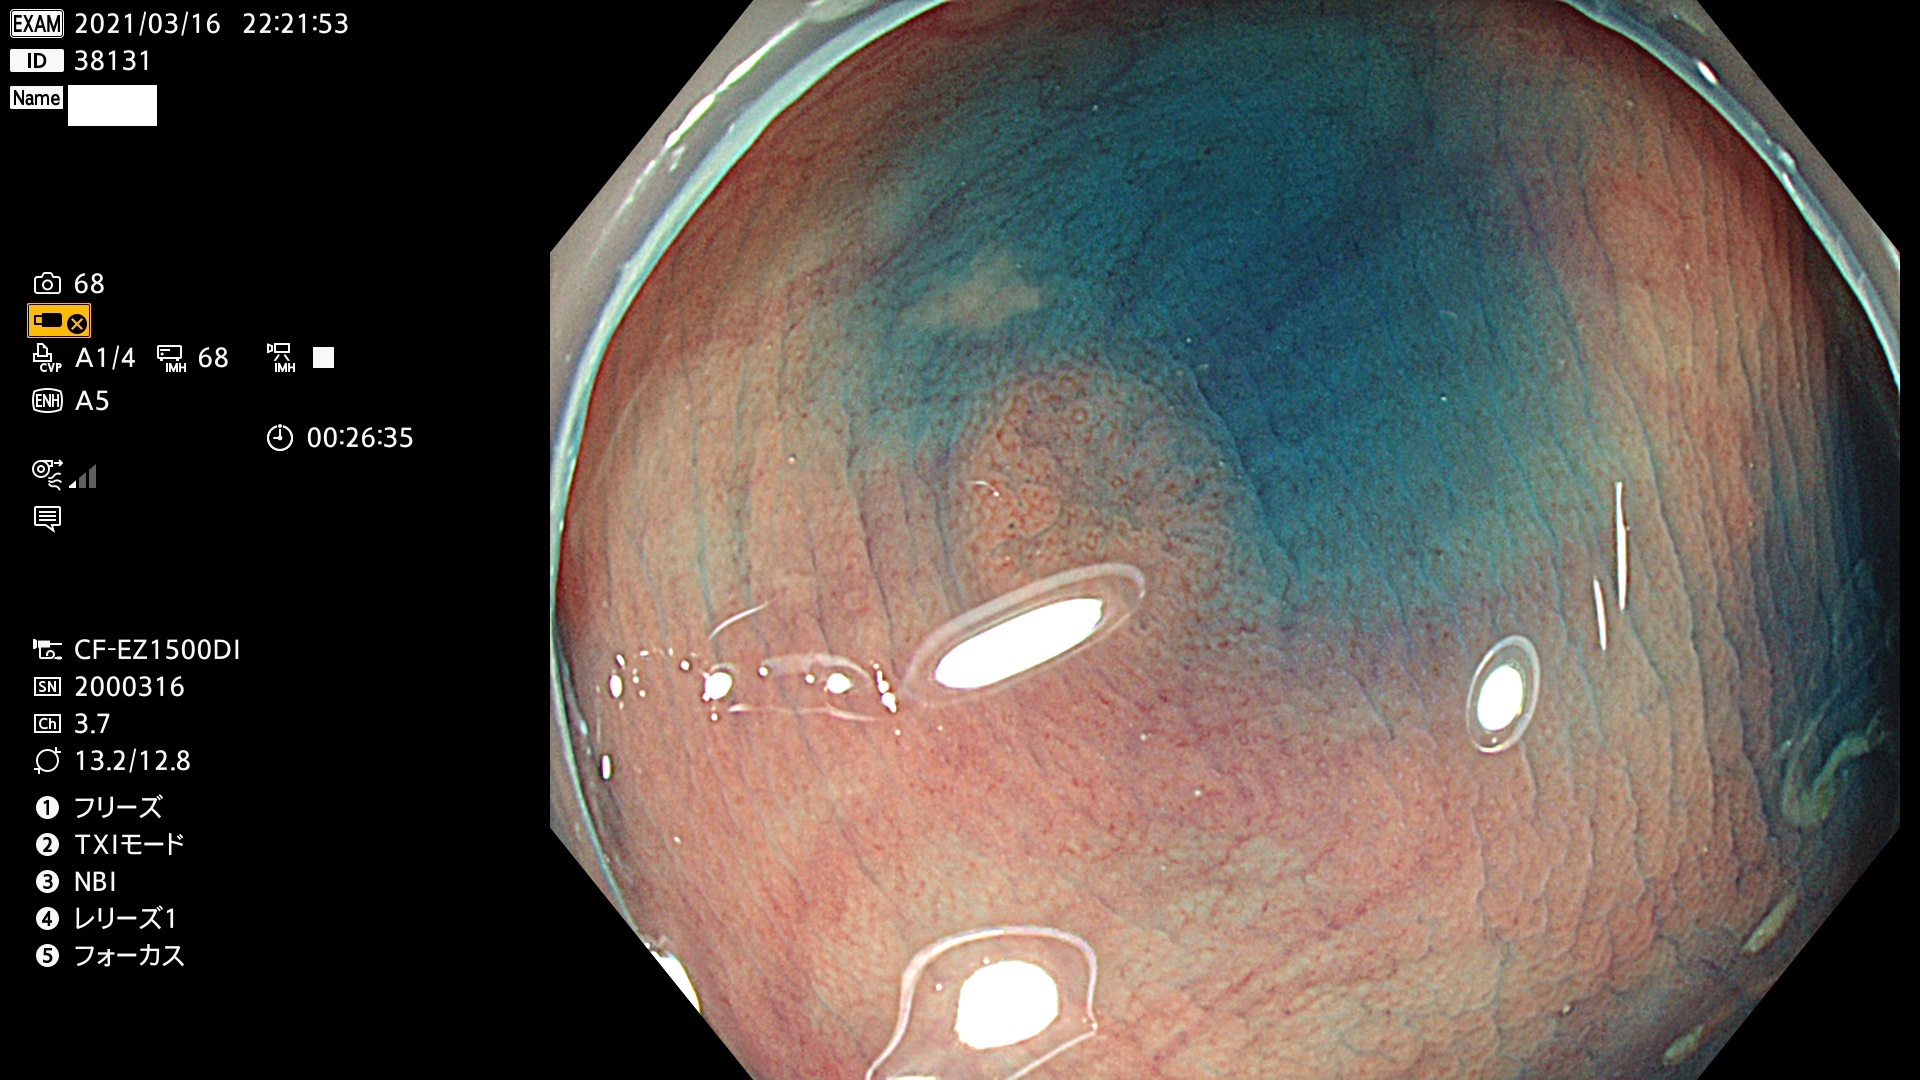

腺腫発見率 72 % (カルテ番号 38100〜38199の100名の方の検査結果で集計)大腸癌検診最新情報

以下のカルテ番号の方に腺腫(Adenoma,Group3〜5)が見つかりました(集計法)

38101 38103 38104 38106 38107 38108 38109 38110 38111 38112 38113 38114 38115 38117 38118 38122 38123 38124 38125 38126 38127 38128 38130 38131 38132 38135 38137 38138 38140 38141 38142(SSAPのみ) 38143 38144 38145 38146 38147 38148 38149 38150 38151 38152 38153 38154 38157 38158 38160 38161 38162 38164 38165 38166 38167 38168 38169 38172 38176 38177 38178 38181 38182 38183 38184 38187 38189 38190 38191 38192 38193 38194 38195 38196(SSAPのみ) 38198

発見困難で危険性の高い平坦型病変(上記100名より抽出) ![]()